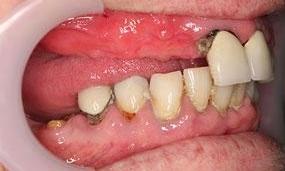

This before and after showcases a comprehensive dental restoration involving root canal therapy, the placement of dental crowns for structural integrity and aesthetics, as well as a full upper denture to restore function and appearance.